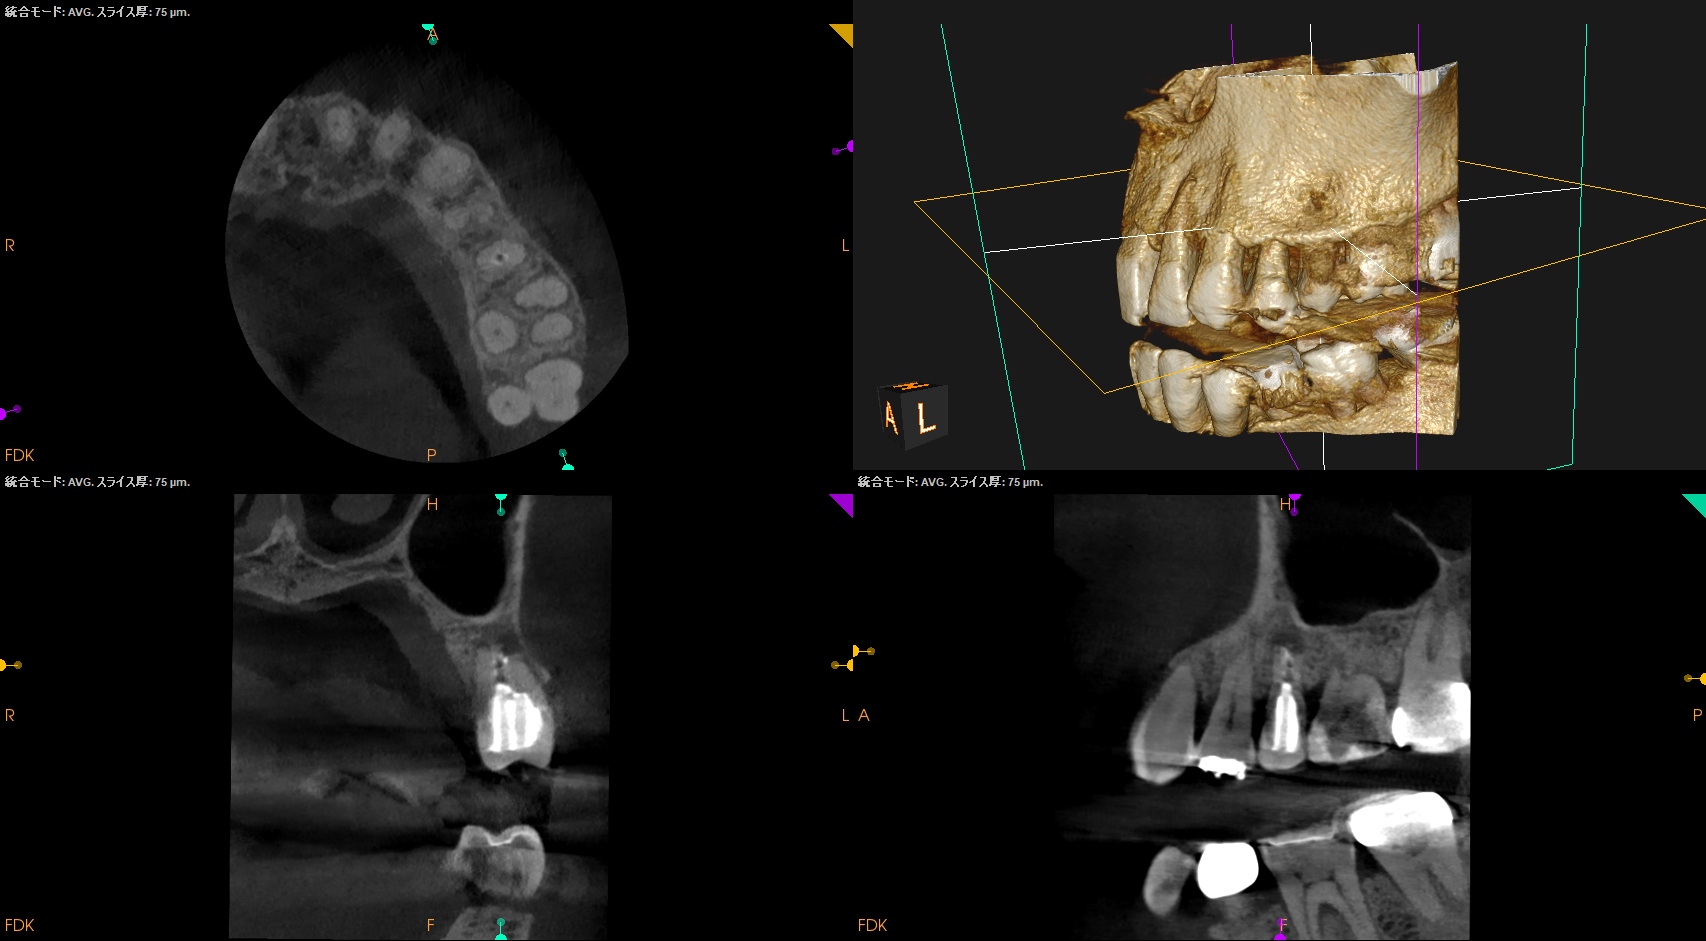

#13 Re-Apicoectomy(2026.4.14)

当該部位をOsteotomyした。

Retroprepした。

脱離した逆根管形成窩洞の中に肉芽が紛れ込んでいた。

これを逆根管形成で除去しつつ、問題がないことを確認した。

Retrofillした。

術後にPA, CBCTを撮影した。

再度、何らかの原因で逆根管充填材が外れないように深く逆根管充填した。

そして、用いる材料も変えてみた。

今回の修正は、

逆根充材の厚みを増してみるというその1点のみである。

やはり浅い逆根管充填はそれが外れやすいというリスクがあるようだ、と私はこのケースから感じた。